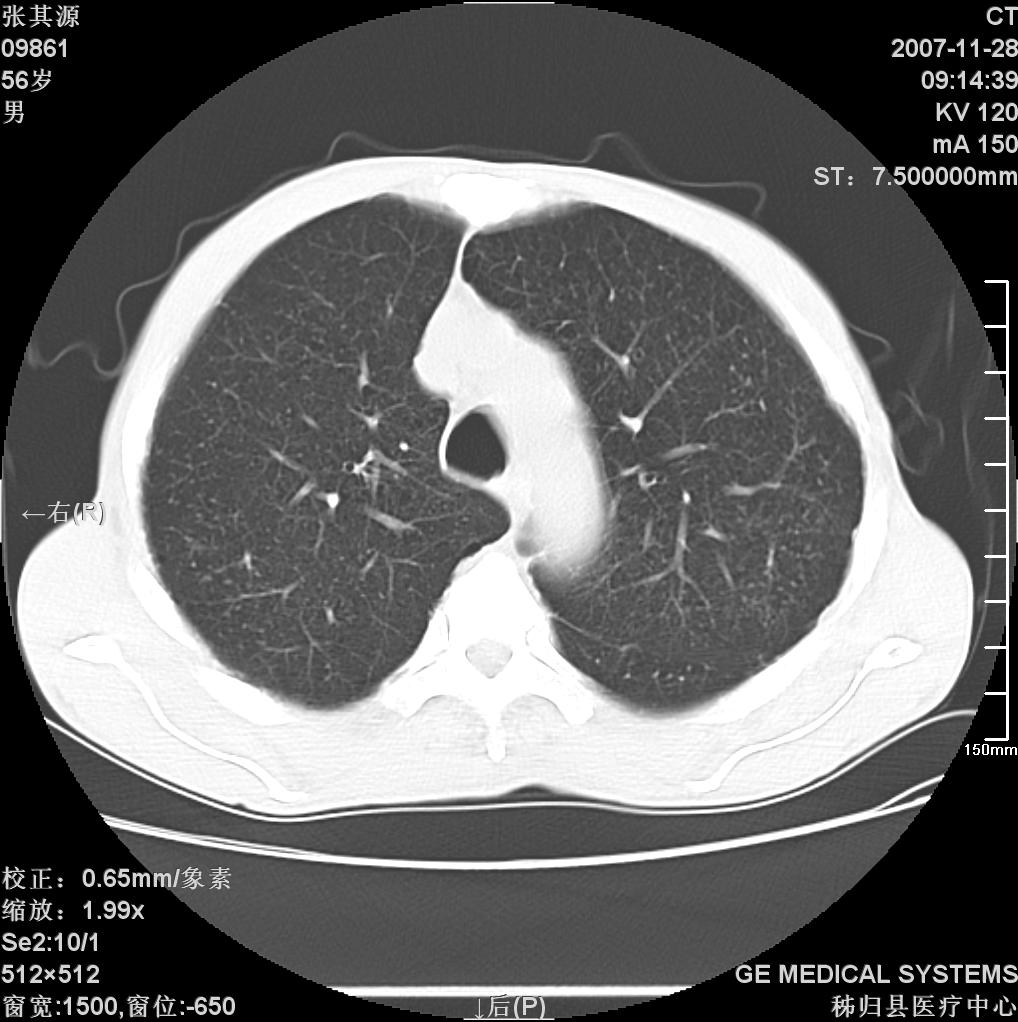

患者因阻塞性黄疸入院,发病前10天持续中等程度发烧.术前检查发现两肺弥漫性病变,请各位大虾会诊,除了考虑急性血源性肺结核外,还有其他什么疾病可能.

补充一下,该患者没有与尘肺相关职业史。请大家帮忙会诊一下,外科医生打算为其做胆总管肿瘤做手术的,现在在等我们的结果。谢谢各位了。

影像符合粟粒型肺tb改变。

双肺多发粟粒样病灶,右肺胸膜下结节样病灶,气管前腔静脉后及隆突下均见肿大淋巴结,结合胆道肿瘤病史首先考虑转移。另外心影密度略低,时间格显示,是否有贫血?查明白再手术吧!